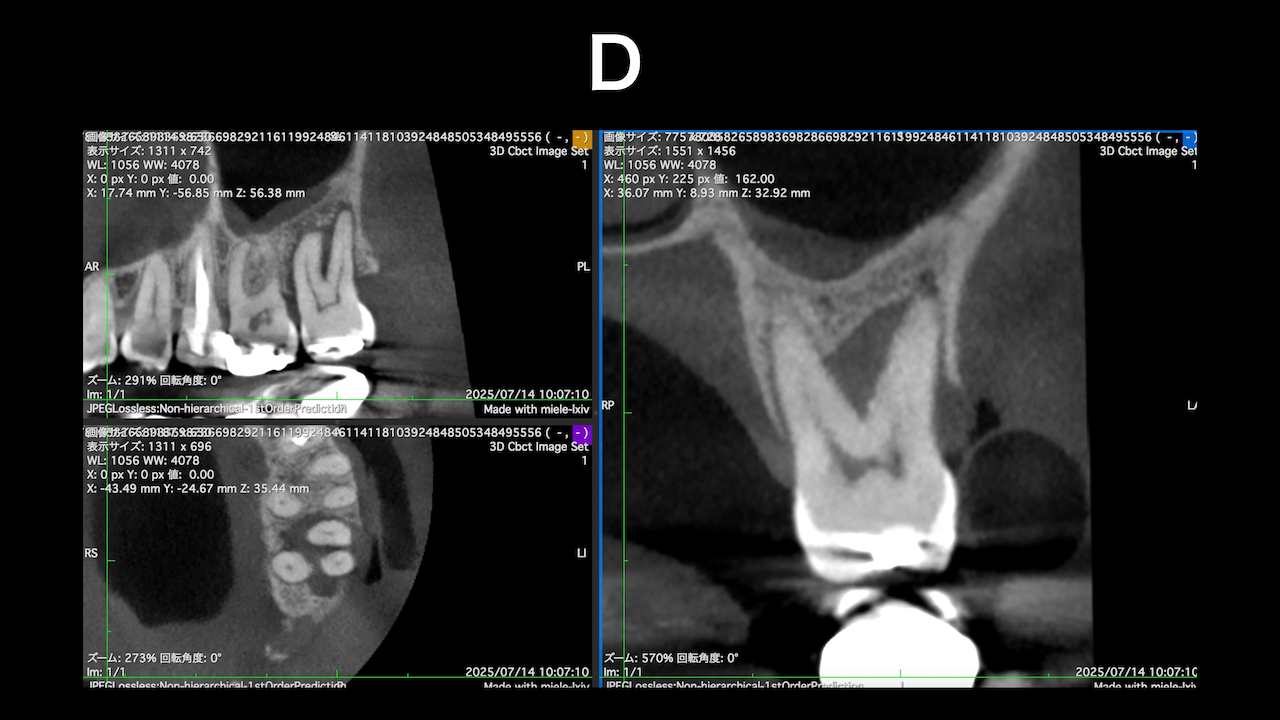

#7がCold testに無反応である。

故に、#7,8の非外科的根管治療を行うことになった。

が、#8のメタルコアは外しにくいだろう。

CBCTでは2本とも口蓋側の皮質骨が消失している。

という絶望的な状況である。

ここから4ヶ月が経過すると…

臨床症状も皮質骨も大きく治癒している。

1年後の予後が気になるところであるが、すごくよくマネージメントできているだろう。